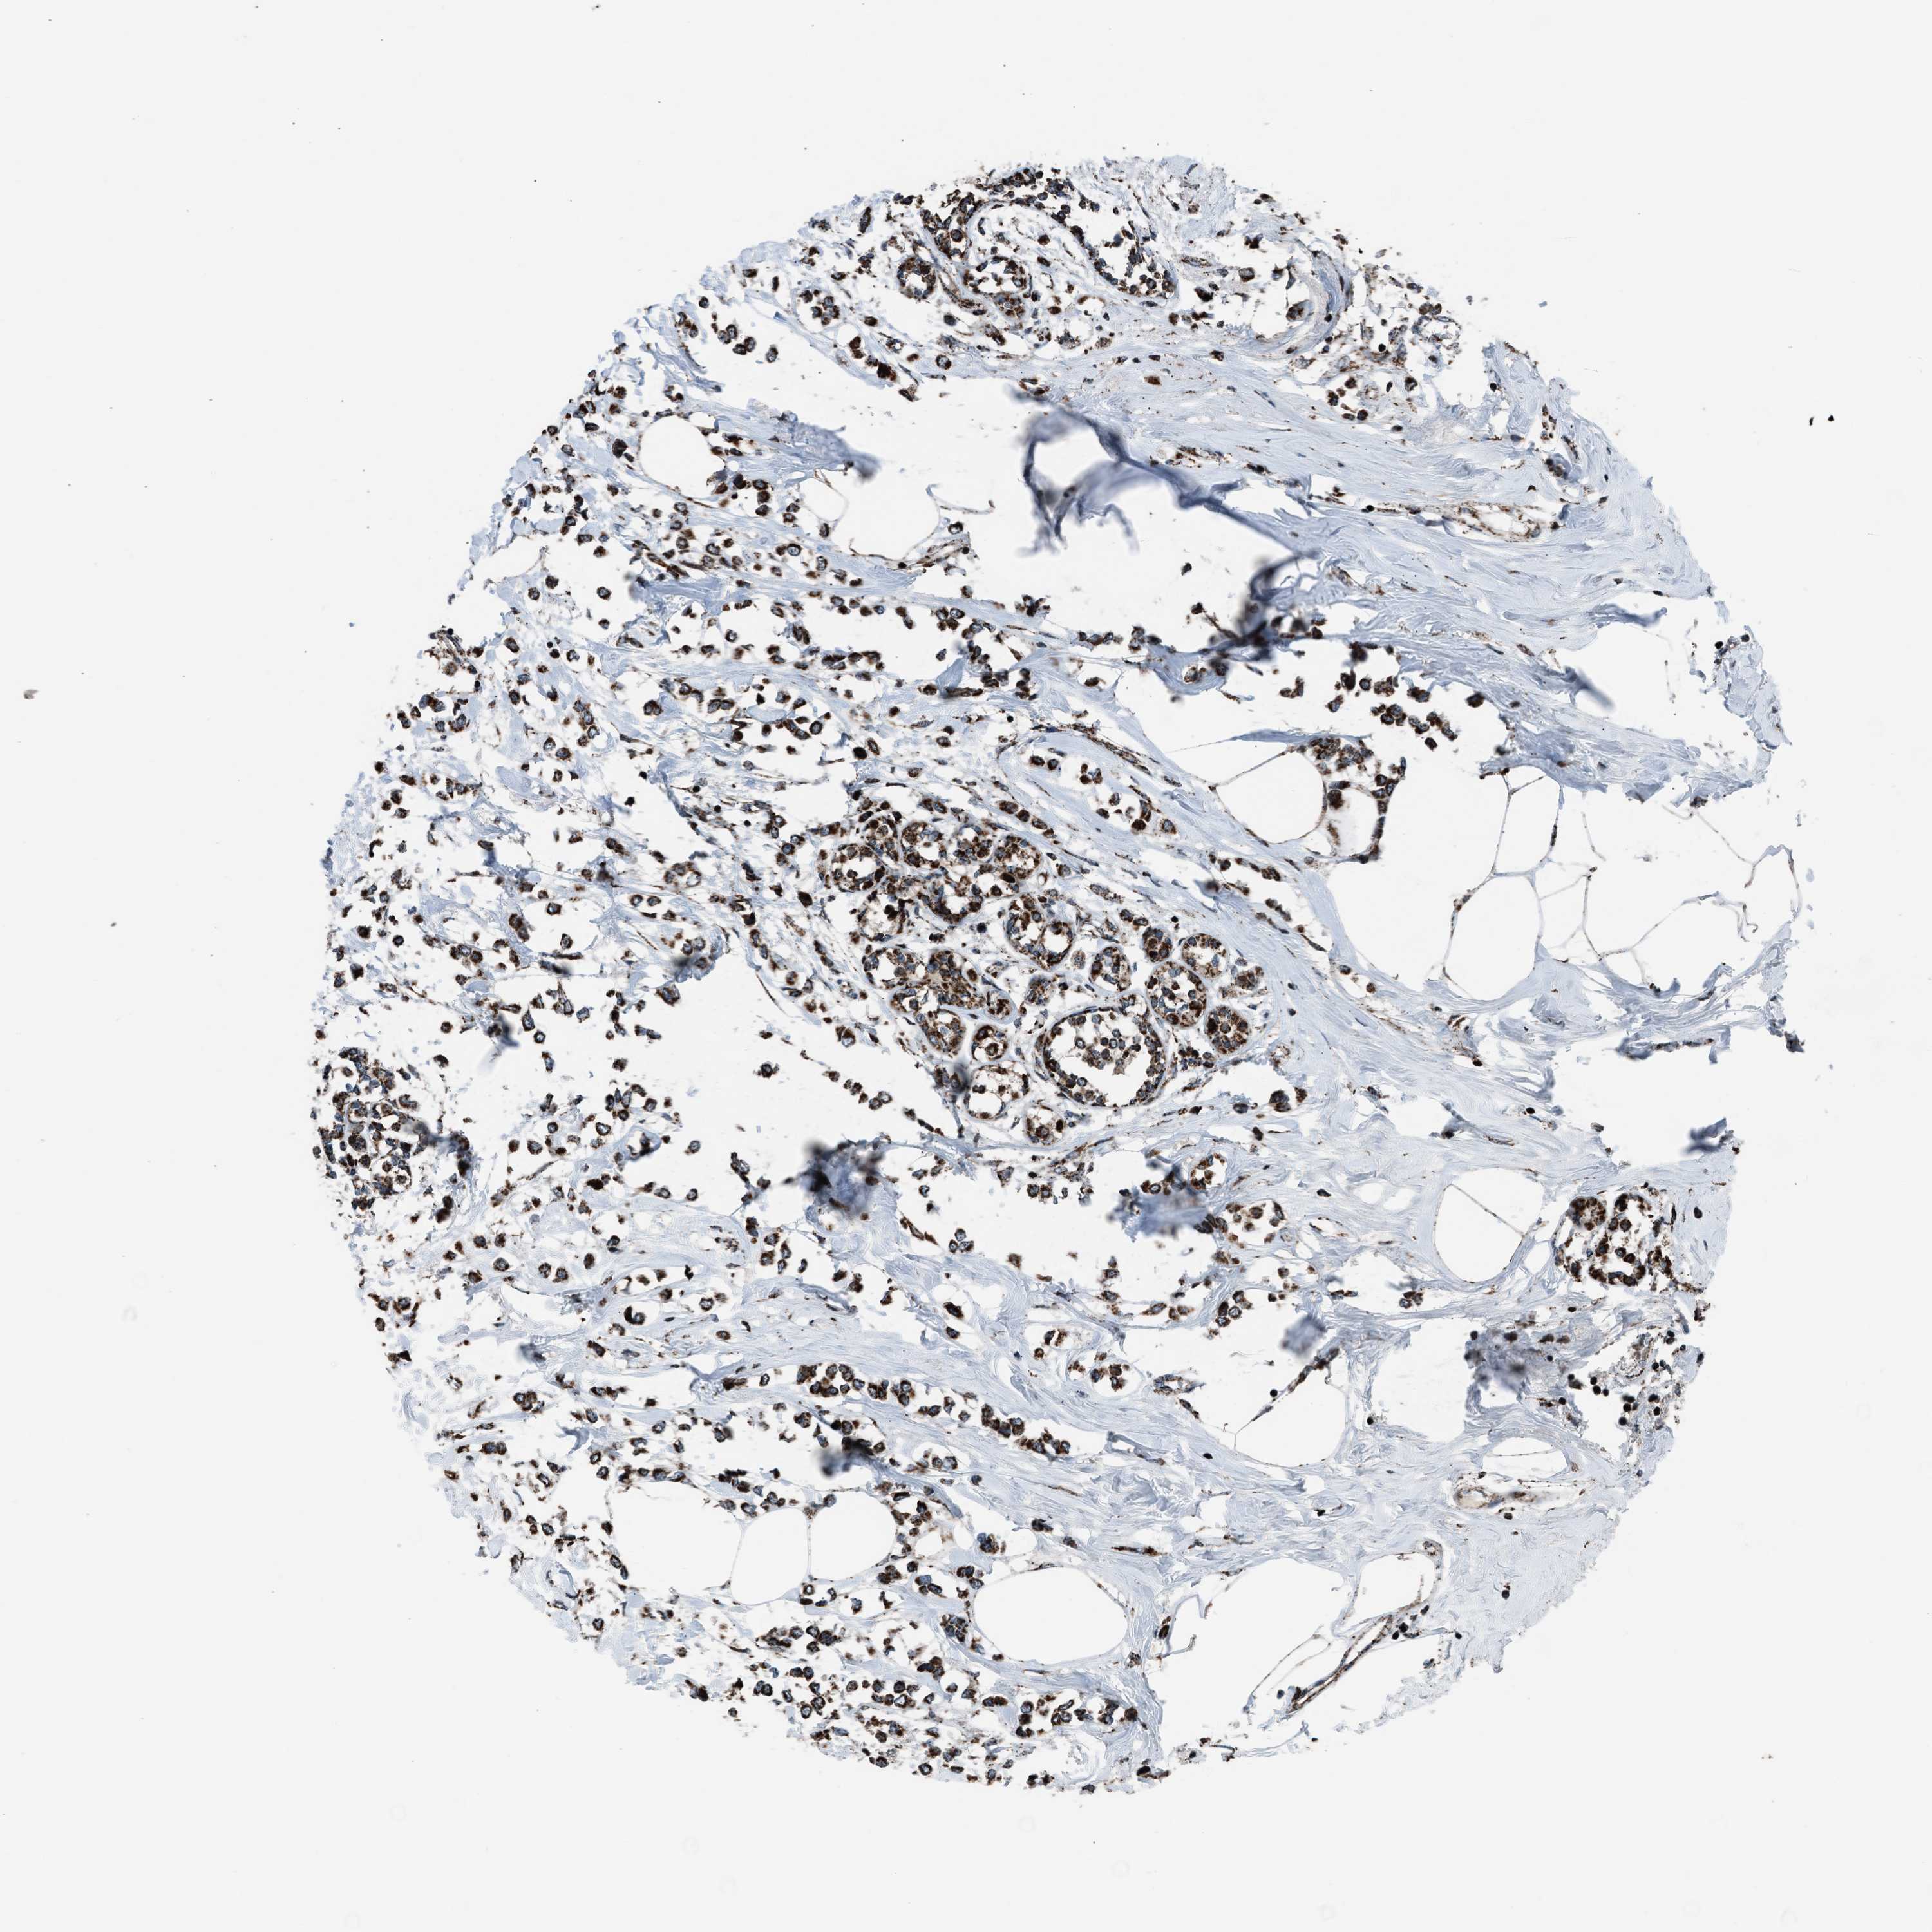

CANCER BREAST CANCER Show tissue menu

BRCA TCGA BRCA VALIDATION PROTEIN EXPRESSION

ANTIBODIES

AND

VALIDATION